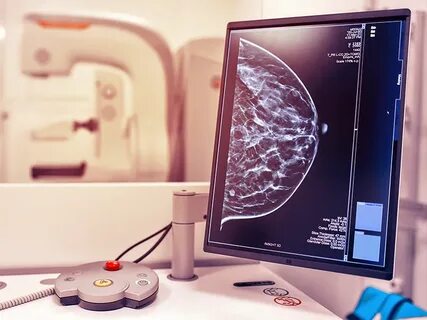

Маммография – это рентгенологическое исследование молочных желез, которое позволяет выявить даже мельчайшие изменения в тканях, неразличимые при пальпации. В возрасте 40 лет и старше риск развития рака молочной железы статистически возрастает. Важно понимать, что на ранних стадиях онкологические заболевания часто протекают бессимптомно, и только высокоточные методы диагностики, такие как маммография, способны обнаружить их на этапе, когда лечение наиболее эффективно, а шансы на полное выздоровление максимальны. Раннее выявление рака молочной железы – это залог успешного лечения и сохранения качества жизни.

Специальной сложной подготовки к маммографии не требуется. Рекомендуется проводить исследование в первой фазе менструального цикла, обычно с 5 по 12 день от начала менструации, так как в этот период молочные железы менее чувствительны и болезненны, а результаты более точны. Перед процедурой не следует использовать дезодоранты, антиперспиранты или лосьоны в области подмышечных впадин и груди, так как они могут исказить результаты. Сама процедура занимает всего несколько минут. Молочная железа помещается между двумя пластинами аппарата и на короткое время сжимается для получения четких изображений. Это может вызвать небольшой дискомфорт или ощущение давления, но обычно не сопровождается сильной болью. В медицинском центре "Томакс" мы используем современное оборудование, которое минимизирует дискомфорт и обеспечивает высокую точность диагностики.